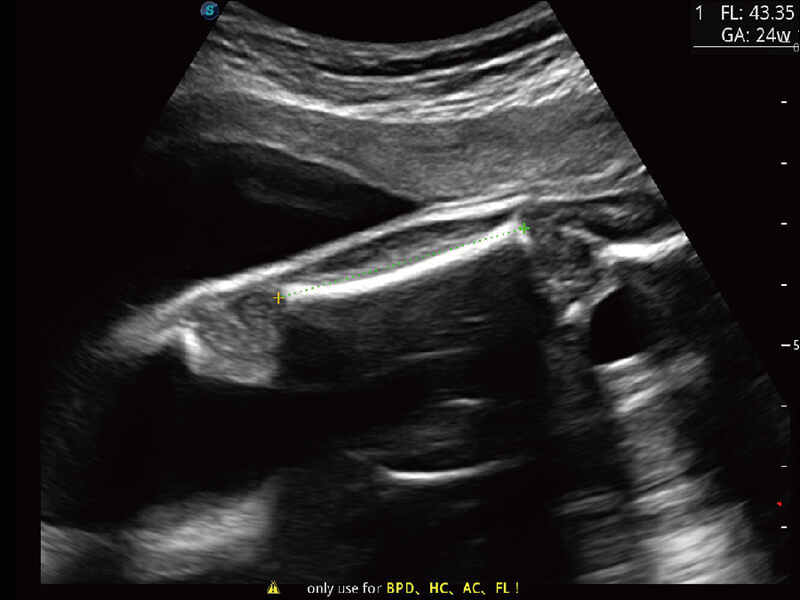

S60探头工艺,从前端信号处理每一个环节采集无损声学数据,真实还原组织原貌,再现解剖细节。

S-Fetus 产科扫查助手

准确率

按键操作